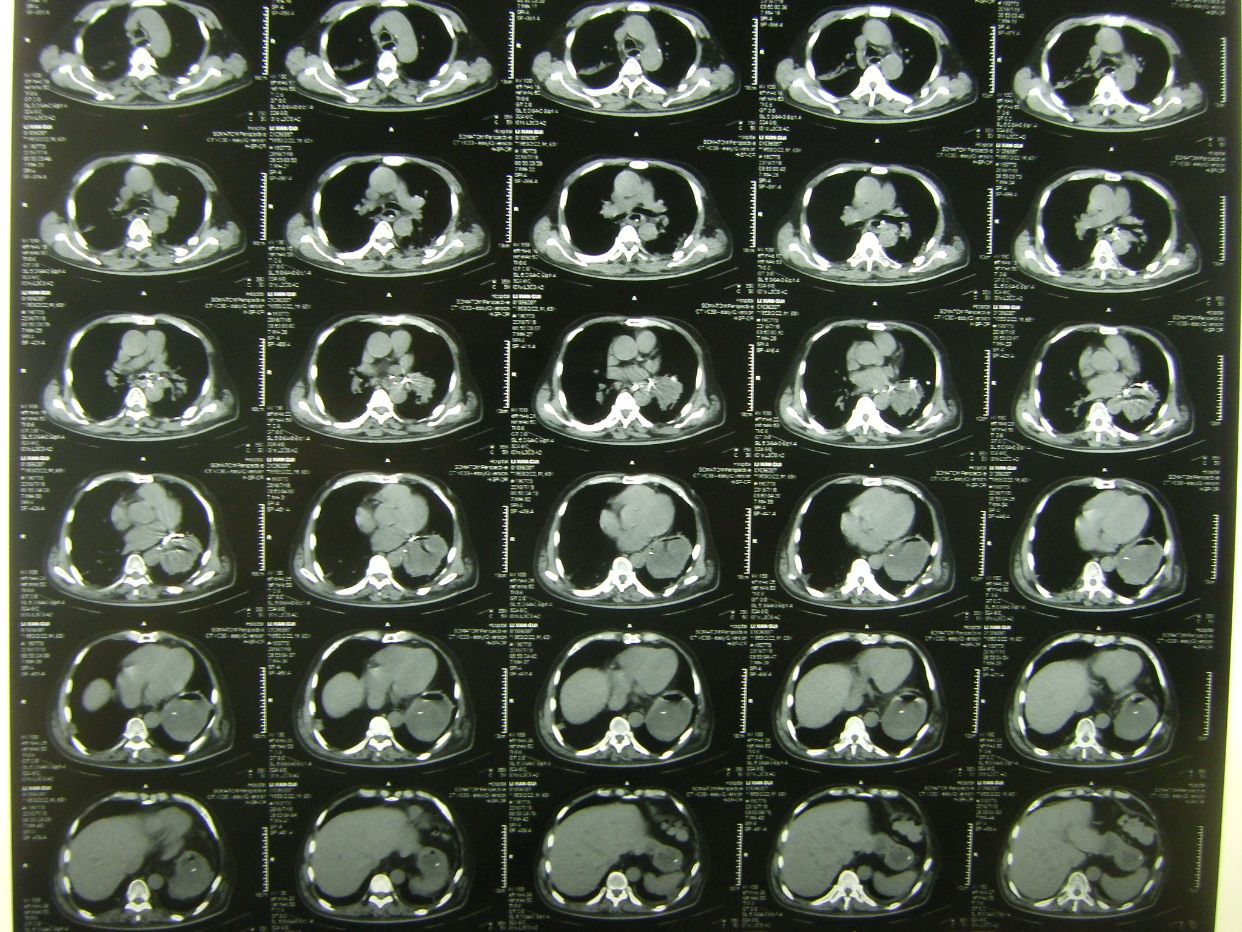

因呼吸急促,氧饱和度低,行胸部CT检查示,双肺野弥漫性斑片状阴影,保留气管插管,拍背吸痰,加强供氧,应用抗炎平喘化痰等药物治疗。

术后半月胸部CT复查示,肺部阴影消退。患者体温血象正常,神志清,遵嘱动作,右侧肢体肌力3级,出院康复。

术后8天,患者出现呼吸困难,氧饱和度下降,胸部CT示左侧肺野消失,考虑胃膈疝并肺不张肺感染。调整体位,拍背吸痰,应用呼吸机辅助呼吸等治疗。

胸部CT复查,肺不张恢复,肺部阴影消退。患者恢复意识,遵嘱动作,呼吸良好,体温血象正常,出院康复。